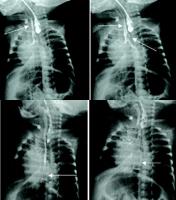

和食管之间的瘘管可为先天性或后天性,并可分为气管-食管瘘和支气管-食管瘘。虽然先天性异常通常在新生儿即可发现,但是前一类型可直到青少年甚至成年才被明确诊断。大部分病例有长期喂奶呛咳史或咳嗽史,常咳出食物颗粒,偶尔合并支气管扩张。